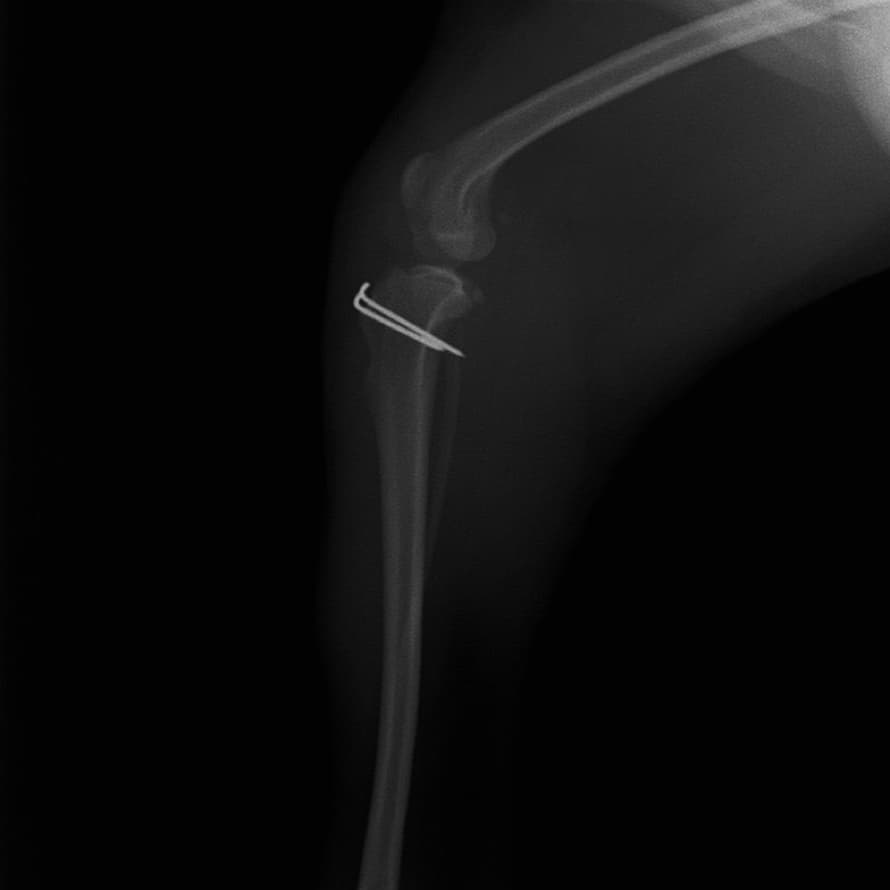

■ 症例22 ポメラニアン 1歳5か月 去勢雄

左後肢の挙上を主訴に来院した。整形学的検査、レントゲン検査より左右の膝蓋骨脱臼(左GradeⅡ〜Ⅲ、右Grade Ⅱ)を認めた。また、脛骨の前方引き出し試験の際に、引き出し兆候は認められないものの、疼痛が認められたため、前十字靭帯の損傷が疑われた。術中における、目視および関節内の操作によって、前十字靭帯の損傷や過伸展といった異常が認められなかったため、膝蓋骨脱臼の整復のみ実施した。手術手技は縫工筋及び内側広筋の解放、脛骨粗面の外側転位、滑車ブロック形造溝術、内外側関節包の縫縮を実施した。本症例は跛行もなく経過良好である。しかし、頸骨高平部の角度(TPA)が 右26.2°、左24.9°であり、解剖学的に前十字靭帯損傷のリスクが高いことから今後の経過に注意が必要である。